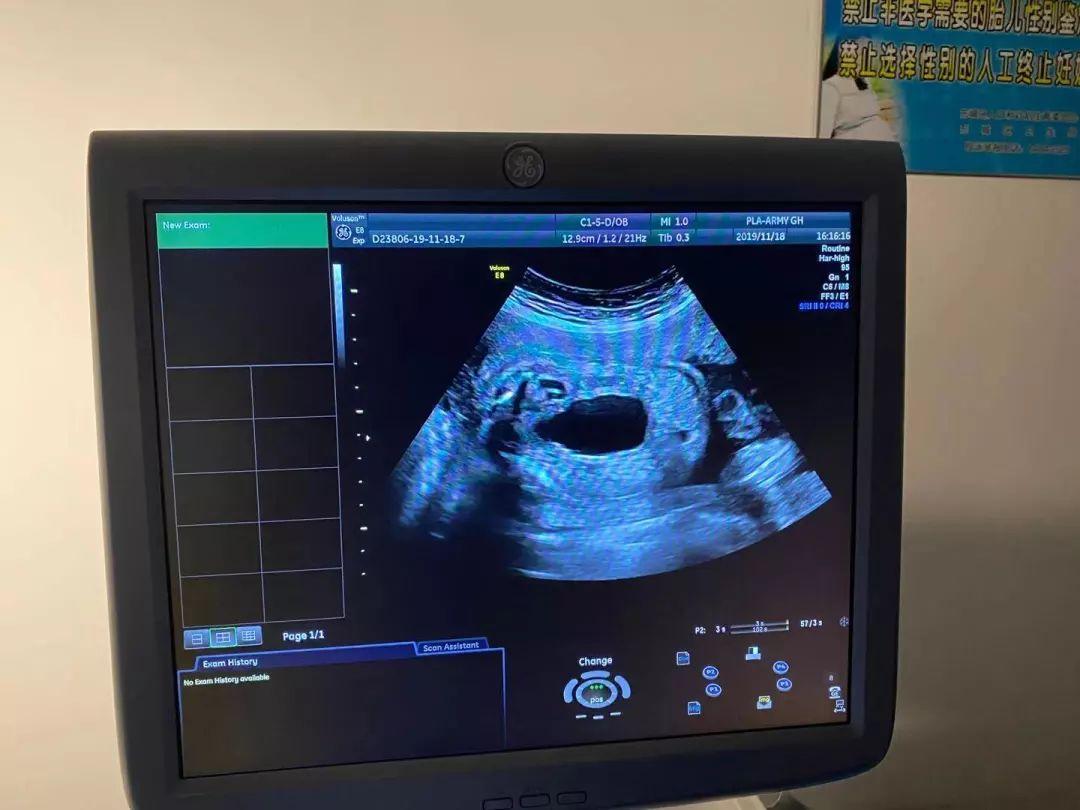

今天孕二十八周多了,打了彩超,大家看看男孩女孩

28周胎儿彩超